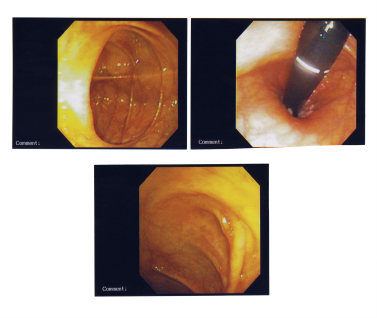

Колоноскопия

Процедуры для изучения внутри толстой кишки с помощью тонкой, освещенная труба (колоноскопии) вводится в прямую кишку. Если аномальных участков видно, ткань может быть удалена (биопсии) и исследуется под микроскопом, чтобы определить болезнь присутствует. Это полезно в постановке диагноза воспалительных заболеваний кишечника, рака толстой кишки, и других условий.